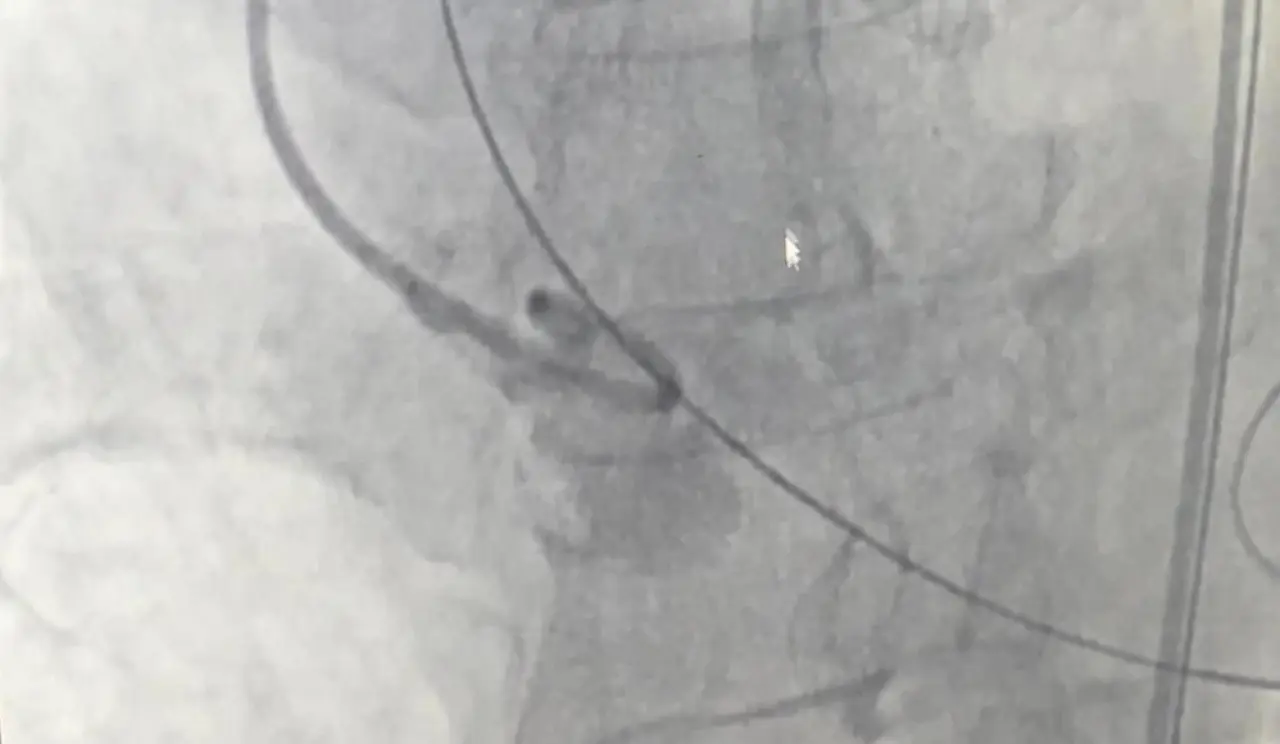

Muzaffer Uslu, göğüs sıkışması ve bayılma şikayetleriyle başvurduğu Merzifon Devlet Hastanesi’nden ileri tetkik ve tedavi için Samsun Eğitim ve Araştırma Hastanesi’ne sevk edildi. Burada yapılan tetkiklerde, hastanın aort kapağının alışıldık şekilde üç değil, dört yaprakçıklı olduğu belirlendi.

Operasyonu gerçekleştiren Samsun Üniversitesi Tıp Fakültesi Kardiyoloji Ana Bilim Dalı Öğretim Üyesi Doç. Dr. Mustafa Yenerçağ, “Hastamızda yaptığımız değerlendirmelerde, toplumda 100 bin kişide yalnızca 4 kişide görülen ‘quadricuspid’ yani dört yaprakçıklı aort kapağı tespit ettik. Literatür taramalarımızda bu tür kapağa TAVİ işlemi yapılan sadece 17 vaka bulabildik. Türkiye’den ise böyle bir vaka kaydına rastlayamadık,” dedi.

Yenerçağ, hastanın yaşı ve açık kalp ameliyatının taşıdığı yüksek risk nedeniyle TAVİ yöntemini tercih ettiklerini belirterek, “Açık ameliyat yerine kateter yardımıyla yapılan kapalı yöntemle başarı sağladık,” dedi.